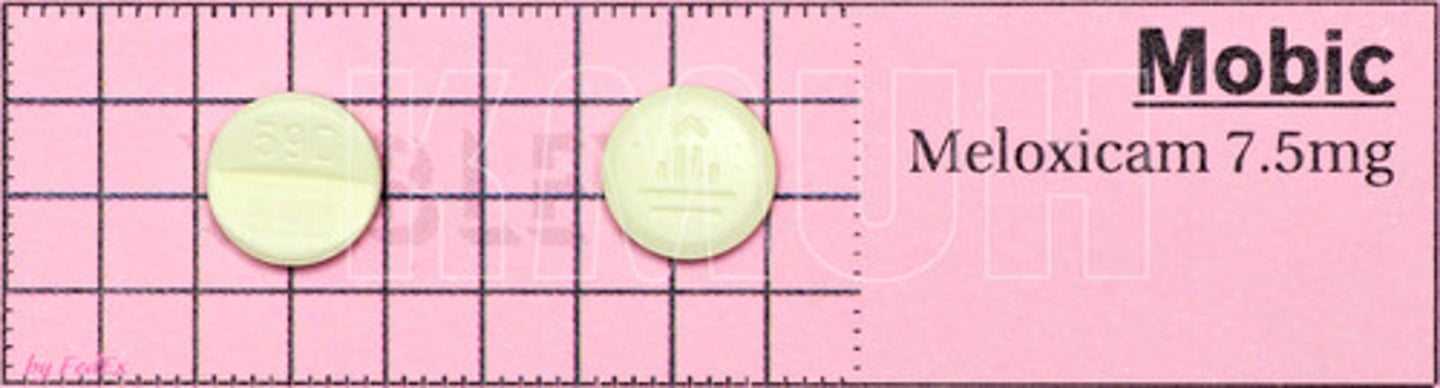

Meloxicam

Brand: Mobic

Class: NSAID

Drug Interactions:

1) Can lead to higher Lithium Levels

2) Can lead to higher Methotrexate Levels

Interaction: Increased Risk of Bleeding with Coumadin

Indication: Pain/Inflammation Relief

Schedule: NCLM